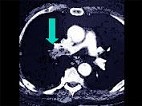

- 多项选择题该病人突发胸部疼痛,进行性呼吸困难, 行X线片检查,提示右下肺病变, 急诊CT平扫加增强,如图所示 ( )

B、SCT增强扫描示右侧肺动脉主干完全性充盈缺损

C、右肺动脉开口处见不规则软组织密度影

D、考虑为右侧肺动脉(中央性)栓塞